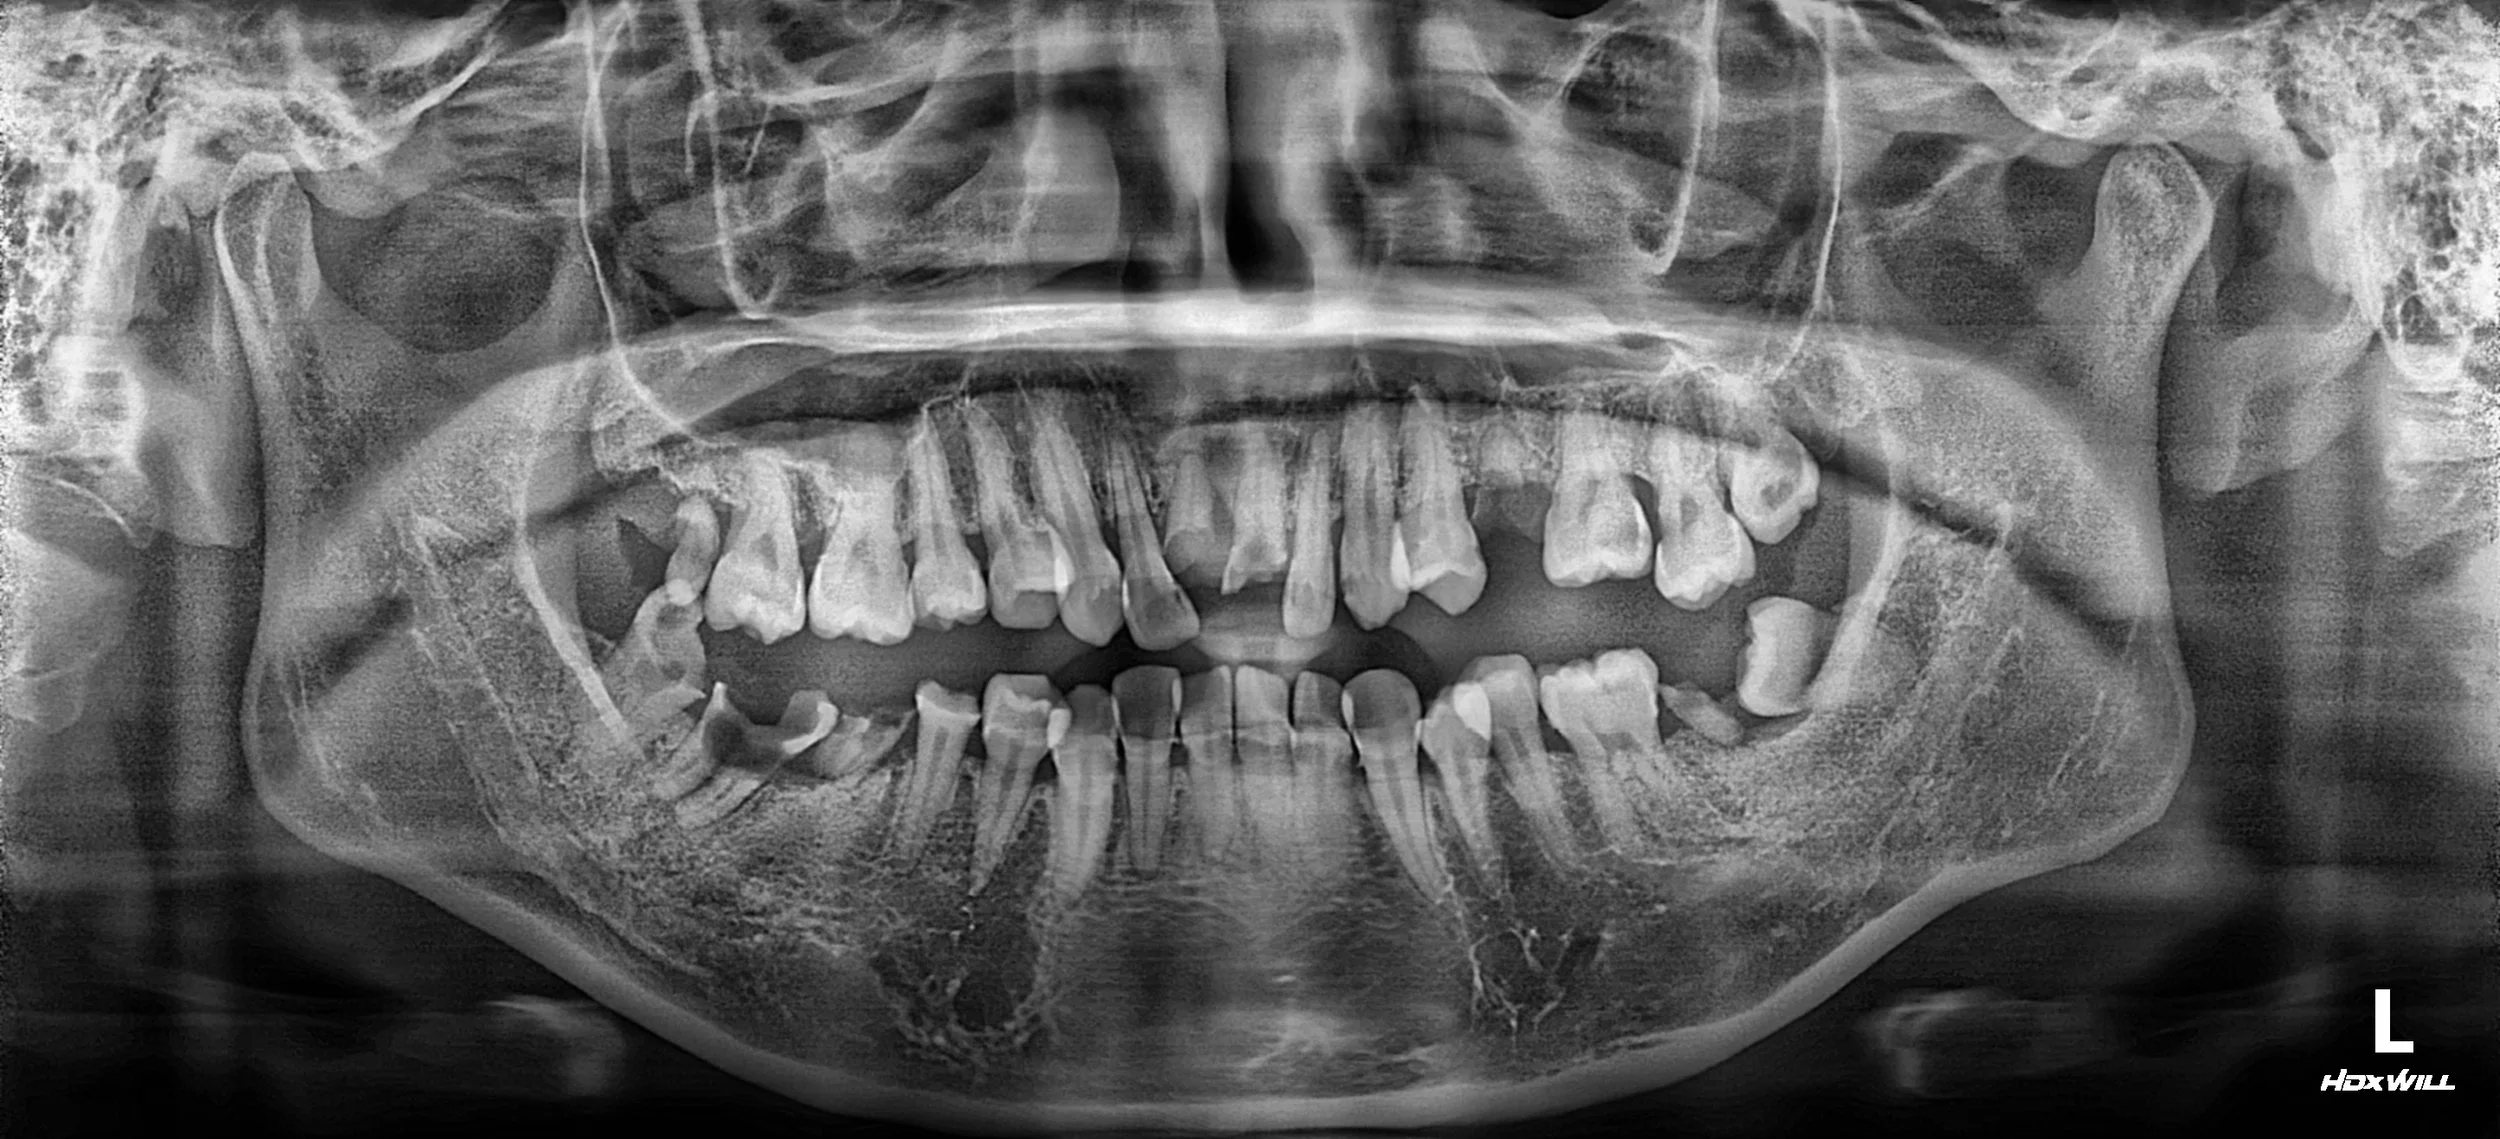

OPG - BEFORE